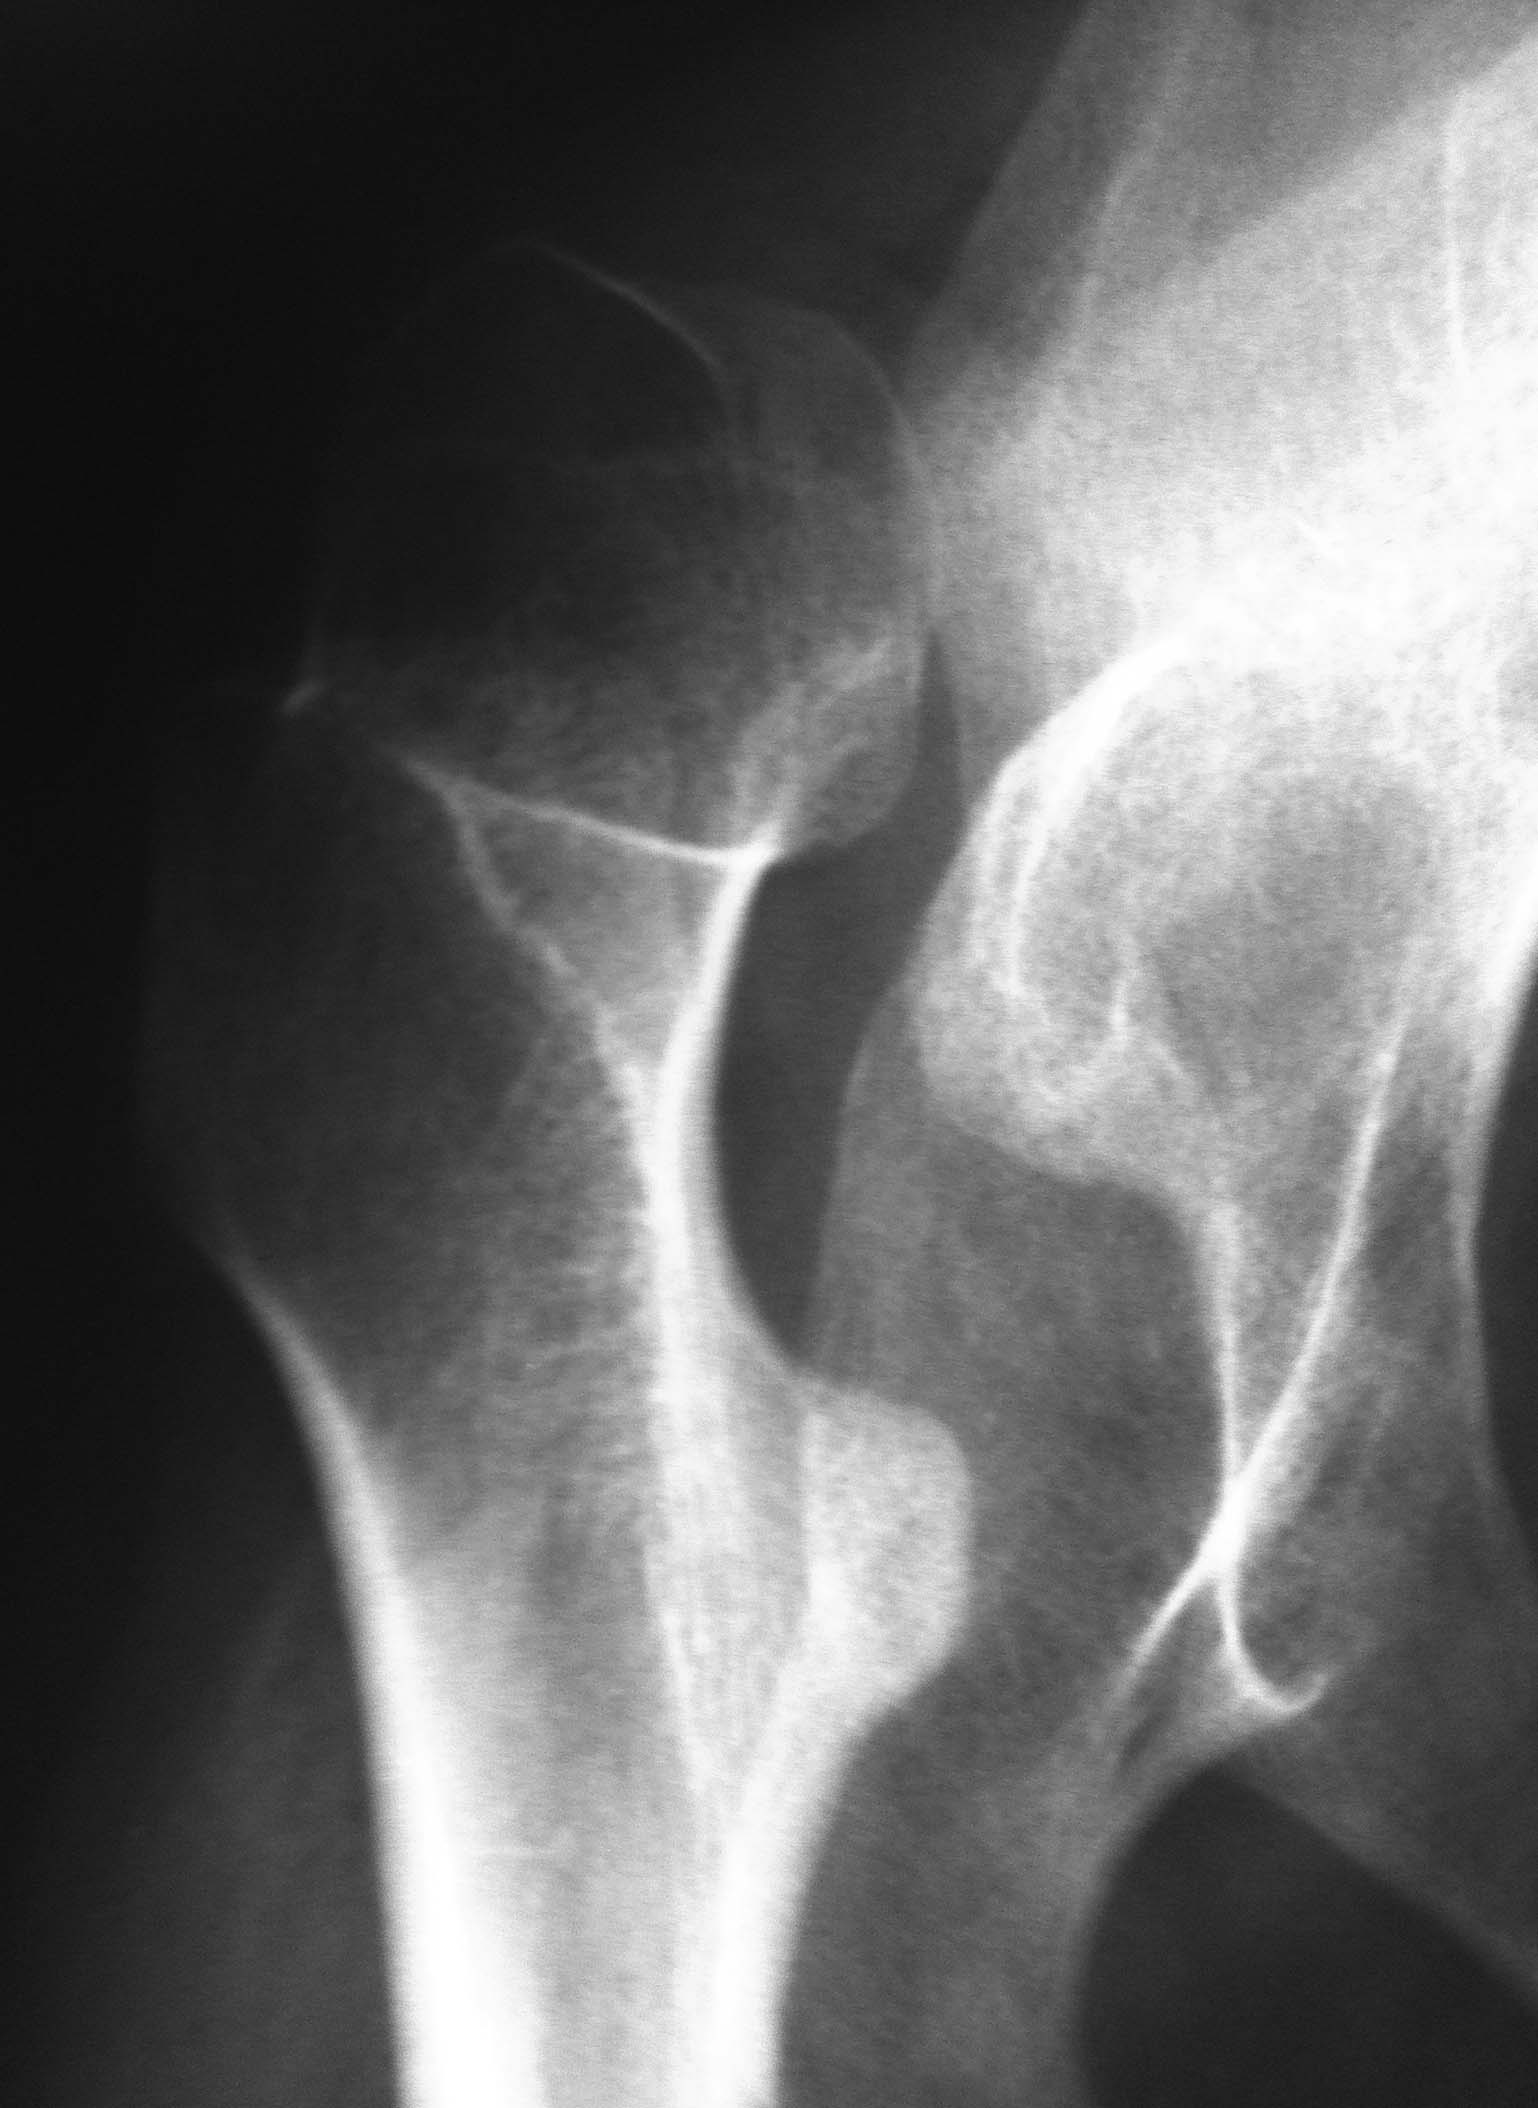

ДЦП, Сколиоз и вывих бедра.

Пациентка 1992 г.р. Болеет ДЦП с рождения. до 2005 г. наблюдалась у неврологов , ходила с поддержкой. В 2005 г. перелом средней трети бедра. Лечилась консервативно в больнице Краснодара.

После лечения постепенно стало наростать укорочение конечности и искривление позвоночника.На представленных Р-гр состояние на сегодняшний день.больная занимает вынужденное полулежачее состояние.Вопрос - где нибудь на просторах РФ могут помочь?????